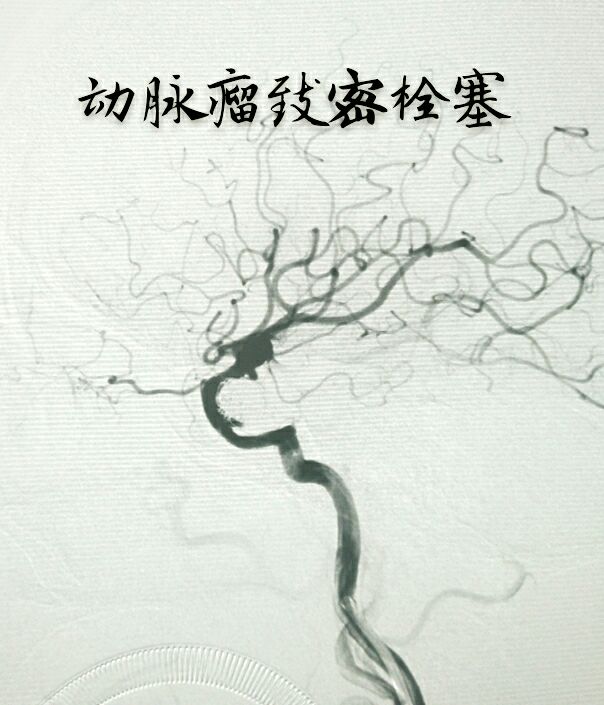

病例二:右侧前交通动脉瘤,宽颈,累及双侧大脑前动脉A2段

支架辅助下致密栓塞动脉瘤,难点:通络迂曲,使用8F GUIDING置于颈内动脉C2段,内套6F Navien置于海绵窦段完成